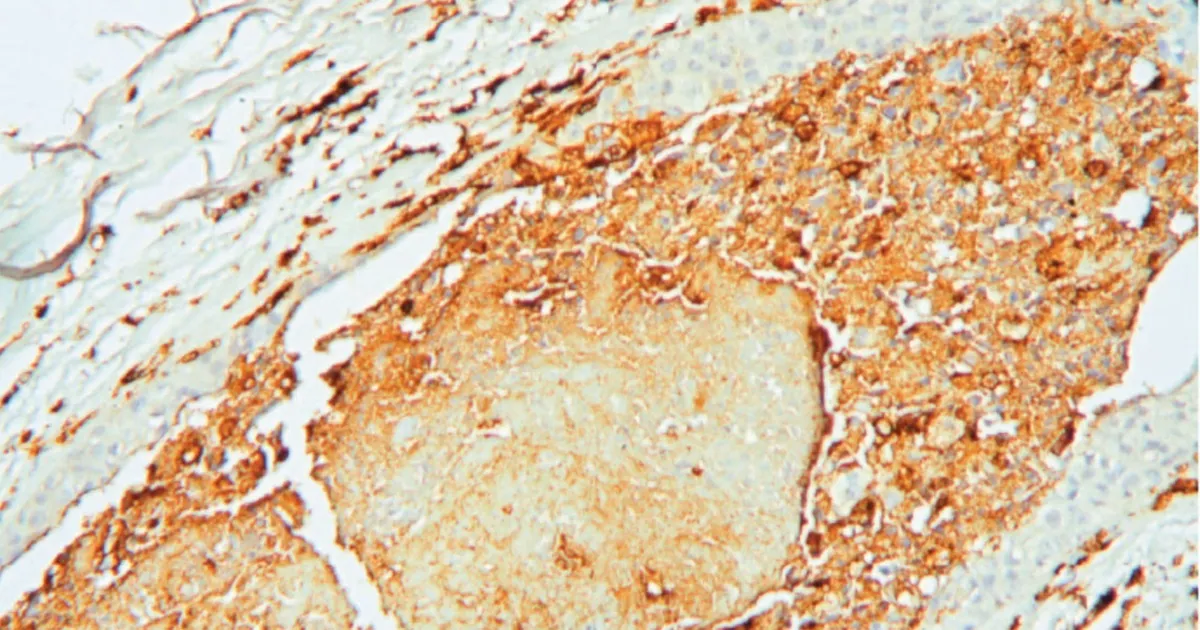

عند فحص الدماغ، اكتشف الباحثون أن الخلل يتركز في منطقة الوطاء، وتحديداً في نواة تسمى النواة المجاورة للبطين. هذه النواة هي جزء أساسي من المحور العصبي الهرموني الذي ينظم الاستجابة للتوتر، والمعروف باسم محور الوطاء-النخامية-الكظرية.

أظهرت الصور المجهرية أن الخلايا العصبية في هذه المنطقة كانت في حالة فرط نشاط مستمر، ولكنها في الوقت نفسه تنتج كميات قليلة من الهرمونات. وهذا يعني أنها كانت تعمل باستمرار دون أن تتمكن من تنظيم إفراز هرمون التوتر بشكل صحيح.